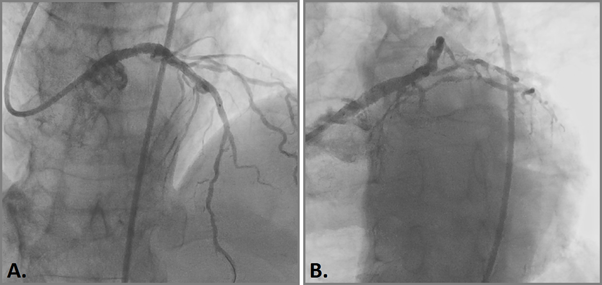

The patient underwent endovascular rotational atherectomy followed by stenting of the affected segments of the coronary arteries. The intervention was carried out under the control of optical coherence tomography (OCT). Initially, the right common femoral artery was punctured under local anesthesia and a 7F introducer was placed. Next, the guide catheter was placed at the mouth of the LCA. The coronarogram revealed 80% calcified stenosis in the terminal LCA OS with a transition to the proximal segment of the LAD and 90% calcified stenosis in the middle segment of the LAD (Figure 1). Using a microcatheter, a conductor was introduced into the apical segment of the LAD. Next, the destruction of calcified atherosclerotic plaques in the LCA and LAD was performed using the Rotablator system of rotational atherectomy (Figure 2), after which, under OCT control (Figure 3), predilatation of the stenotic areas of the LAD with a 2.25x15 mm balloon catheter was performed, followed by positioning and implantation in the area of residual stenoses in the middle segment of the LAD, the proximal segment of the LAD and the OS of the LCA of everolimus drug-eluting stents 3x38 mm and 4x38 mm, respectively. Then, post-dilatation of the stented segments with 3.5x20 mm, 4.5x15 mm balloon catheters and proximal optimization in the LCA OS with a 5x15 mm balloon catheter were performed, achieving a good angiographic result: blood flow in the TIMI-3 arteries. On the control image and OCT control, the stents were fully extended, no signs of dissection were detected, and no residual stenoses were found (Figure 4, 5).

Figure 4 Angiographic result of balloon angioplasty and stenting.

Figure 5 Optical coherence tomography after balloon angioplasty and stenting.